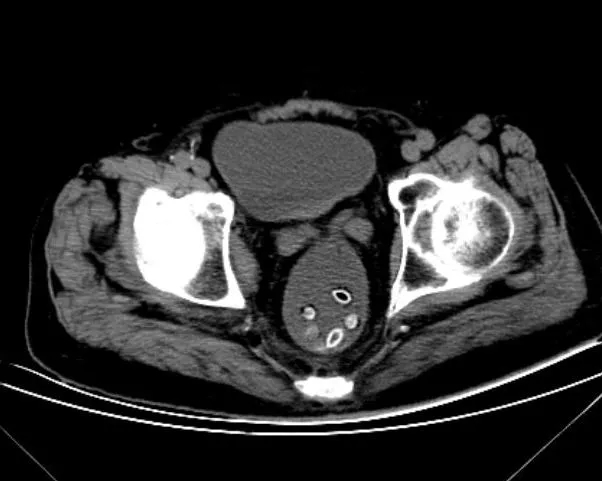

检查后,医生发现洪大爷的下腹部多了一串“珠子”,造成了肠梗阻。

随后,医生组织会诊,从他的肛门里抠出了8颗杨梅籽,经过灌肠处理后,洪大爷腹痛的症状得到缓解。